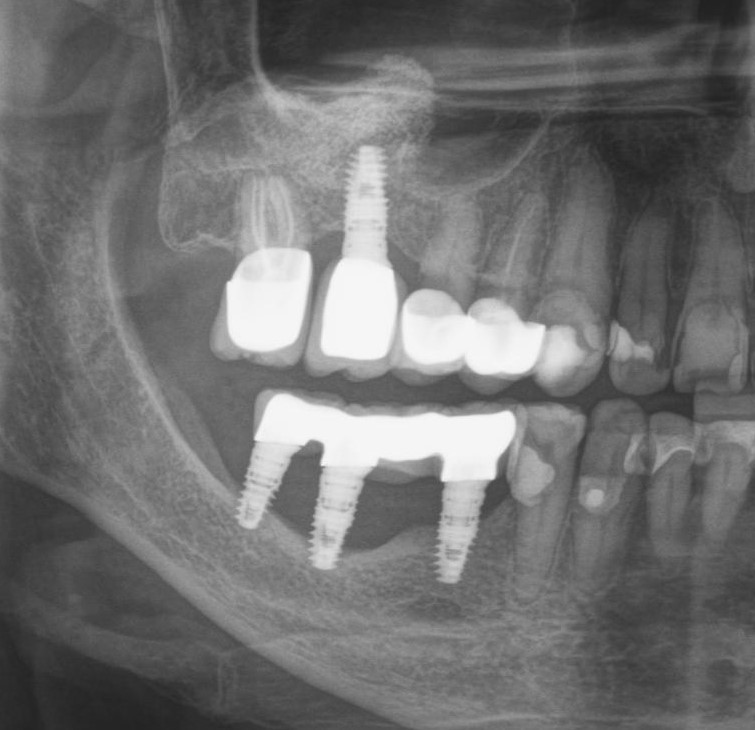

Тут представлена ошибка, как в позиционировании иплантата, так и в изготовлении вот такого великолепного мостовидного протеза.

Кроме уже известной нам цементной фиксации, с выведением материала под десну, меня добила форма этой конструкции. Она идеальна для того, чтобы под протез забивалась пища и хранилась там годами.

На самом деле, если бы был изготовлен мост адекватной формы, без нависающих краев, с хорошей промывной частью и винтовой фиксацией, то можно было бы избежать этой проблемы.

Но с другой стороны, если бы хирург правильно спозиционировал имплантаты, можно было бы изготовить коронки на каждый зуб по отдельности и не извращаться с мостовидным протезом. Это упрощает гигиену и уход за ортопедическими конструкциями.